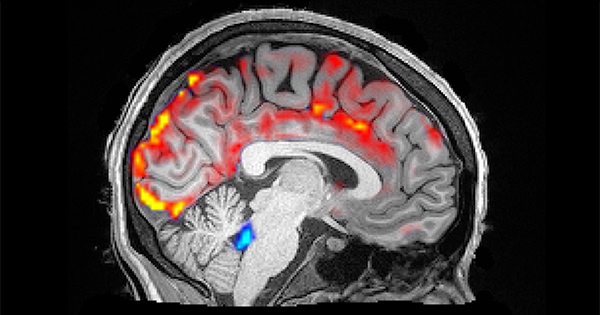

Are you brainwashed at night? (by CSF - CerebroSpinal Fluid)

Hence when your brain is washed at night the concentration of melatonin is 5-20 times as high as blood serum.